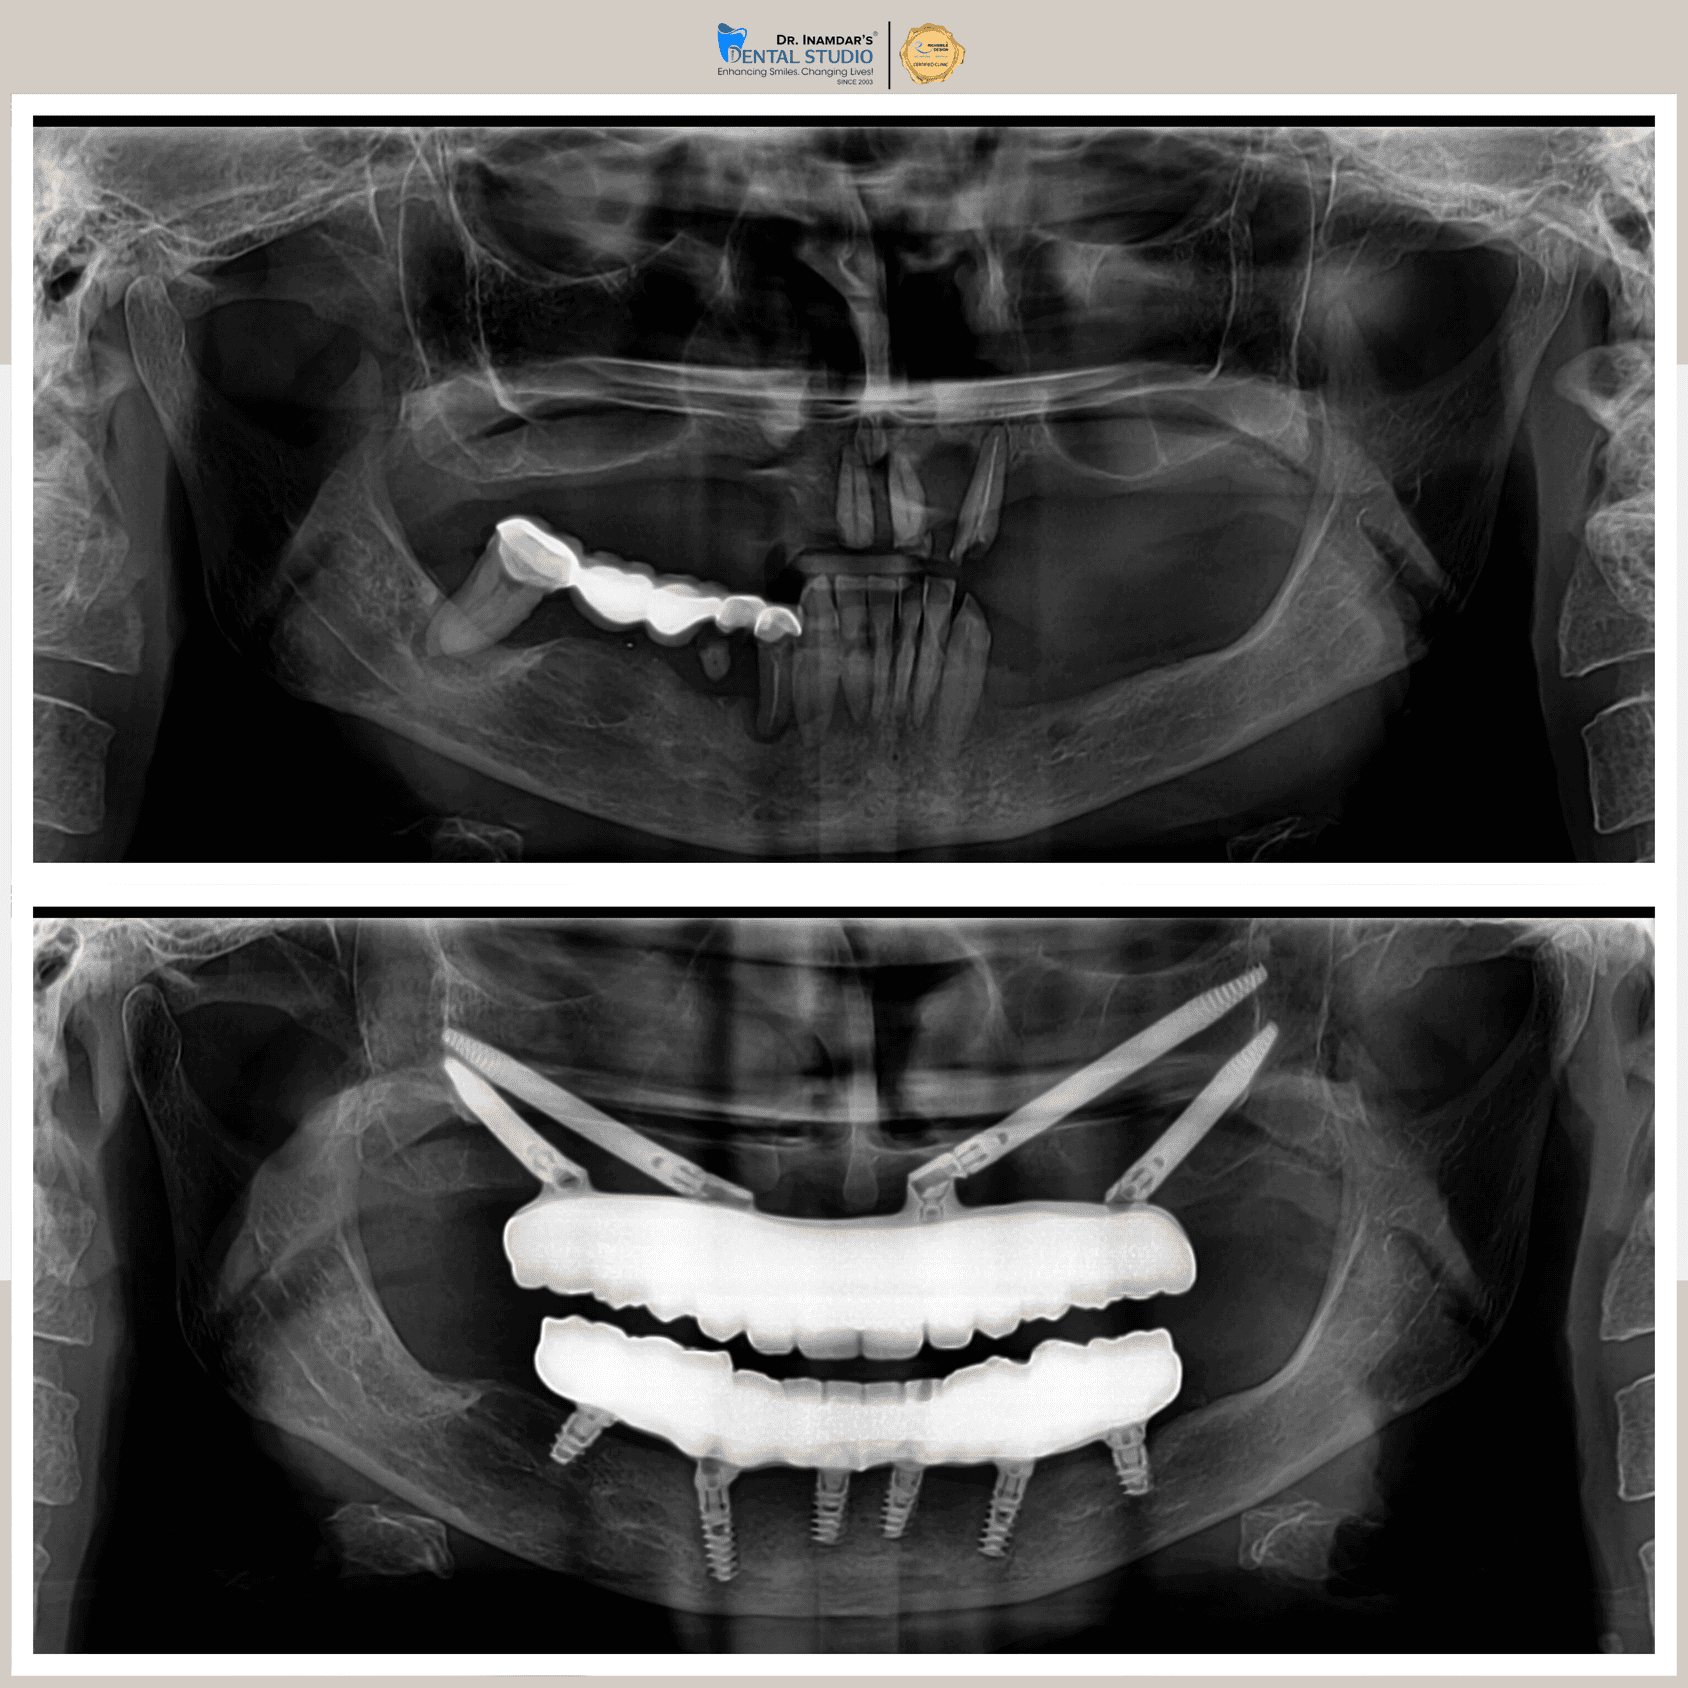

Full mouth dental implants are used to replace all missing teeth in the upper or lower jaw. A series of titanium implants are placed securely in the jawbone, and custom-made ceramic or zirconia crowns, are attached, restoring a full set of functional, natural-looking teeth.

At IDS, we specialize in full mouth dental implants using facially driven, digitally planned workflows for unmatched precision and natural aesthetics. Our approach ensures optimal implant positioning, seamless integration with facial features, and long-lasting, functional results. With a focus on patient comfort, we deliver a personalized and transformative smile makeover experience.

The dental implant procedure typically involves placing the implant into the jawbone, followed by a healing period before attaching the crown.